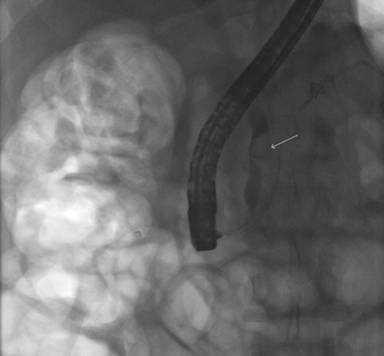

A 42-year-old African American man presented with nonspecific abdominal pain, bloating and dyspepsia for two months. A CT scan of the abdomen showed biliary obstruction with dilatation of biliary ducts, and suggested a soft tissue mass in the pancreatic head. The patient underwent an esophagogastroduodenoscopy with an endoscopic ultrasound (EUS) that revealed a dilated proximal common bile duct and a hypoechoic intraluminal density within the intrapancreatic portion of the common bile duct with post-acoustic shadowing. Subsequently, he underwent endoscopic retrograde cholangiopancreatography, which showed a smooth stricture in the intra-pancreatic portion of the common bile duct suggestive of an extrinsic compression (Figure 1). Cytology of the bile duct brushings was non-diagnostic, therefore, a biliary sphincterotomy with stent placement was performed.

Figure 1. Endoscopic retrograde cholangiopancreatography showing a smooth stricture in the intra-pancreatic portion of the common bile duct. |